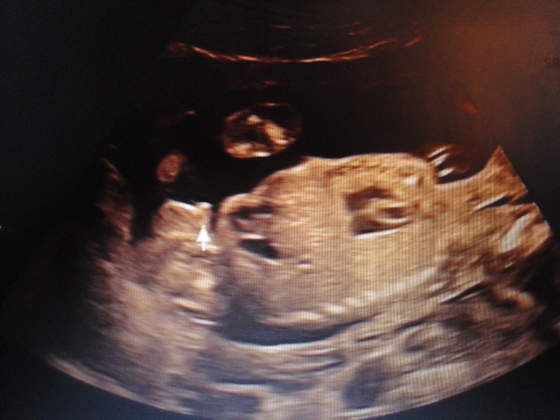

1400 mego Szczęścia